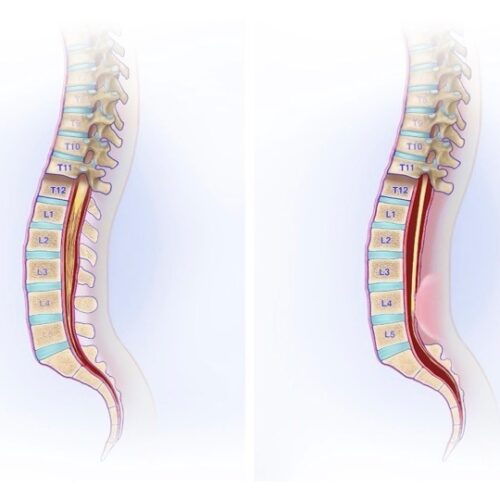

Was bedeutet Spinalkanalstenose?

Es ist eine Kompression des Rückenmarks oder der Nervenwurzeln durch eine Verengung des Wirbelkanals. Entwickelt sich eine...

Dabei handelt es sich um einen Zustand, bei dem das untere Ende des Rückenmarks abnorm tief liegt und im Spinalkanal fest bzw. straff fixiert ist. Meist ist dies eine angeborene Entwicklungsvariante. Es kann auch als verdicktes Filum terminale, fettreiches (fatty) Filum oder...

Die Kleinhirntonsillenherniation ist ein Zustand, bei dem der untere Teil des Kleinhirns (die Tonsillen) durch die Öffnung an der Schädelbasis nach unten verlagert ist. Diese Verlagerung kann den Fluss des Liquor cerebrospinalis (CSF) stören und Druck auf den Hirnstamm ausüben.